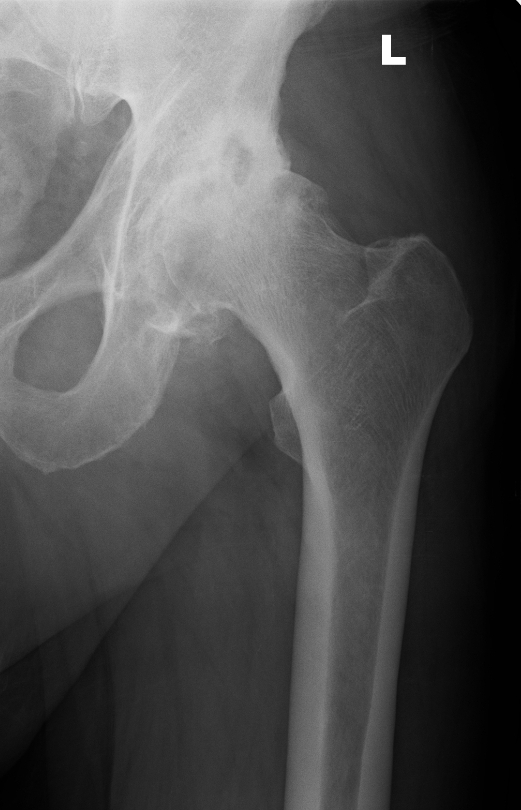

Below you see X-ray examples of patients with severe osteoarthritis of the hip before (Fig 1) and after (Fig 2) total hip replacement, and of the knee before (Fig 3) and after (Fig 4) total knee replacement that have been successfully treated under Mr Weitzel’s care.